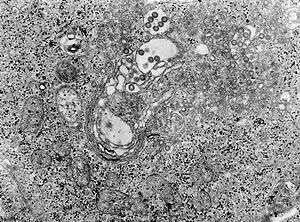

TEM micrograph of tissue infected with Rift Valley fever virus | |